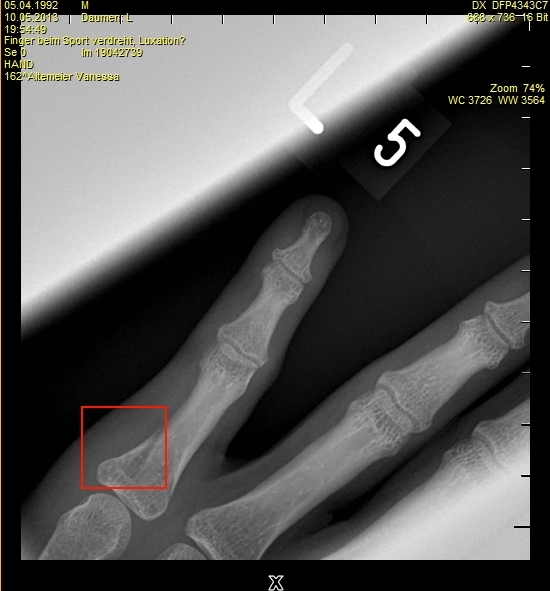

da ist mein finger im roten bereich der bruch. der geht noch auf die rückseite (nicht sichtbar) noch weiter

Und das ist doch nicht der Daumen!? -

die frau hat mich geröncht? und daumen l heißt nur linke hand. da ist nicht der finger gemeint.

Auf jeden Fall fies da so am Gelenk.

so tut es auch weh.